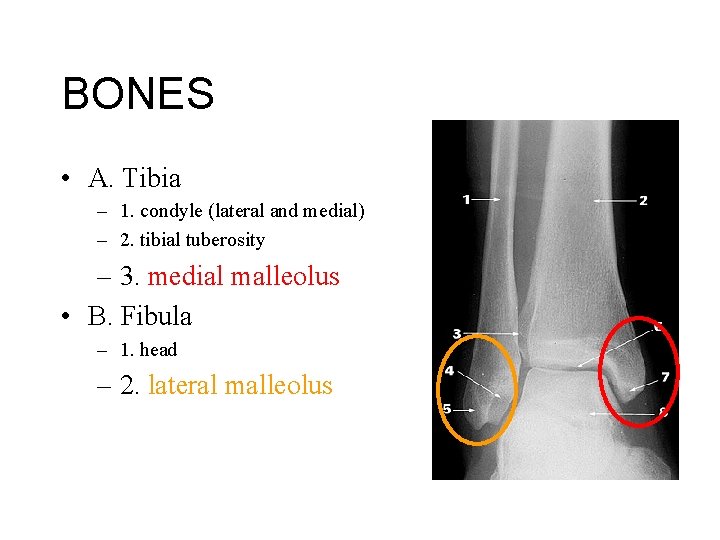

BONES • A. Tibia – 1. condyle (lateral and medial) – 2. tibial tuberosity – 3. medial malleolus • B. Fibula – 1. head – 2. lateral malleolus